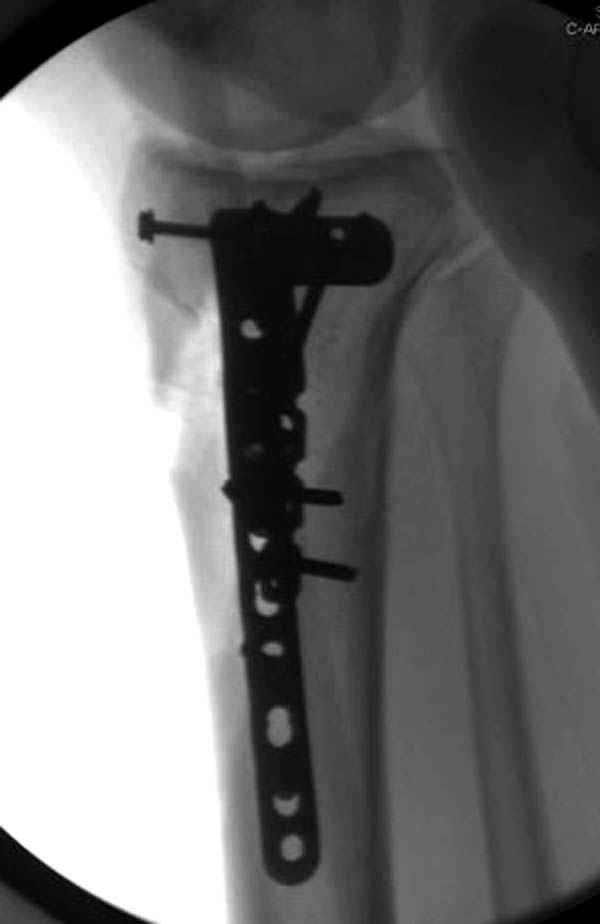

Уважаемые коллеги! В прошлую пятницу больной прооперирован - как и планировалось мыщелковая LCP от ChM. Малоинвазивно не получилось - один большой доступ :(. (но с минимальным скелетированием б/б кости). Наружный мыщелок собрали, но по контролю видно, что задне-медиальный отдел метаэпифиза смещен. Фиксировать не стали (?). 4-е сутки после операции - по м/тканям без проблем. Дополнительная иммобилизация синтетическим тутором.

Интересно услышать ваши мнения, анализ ошибок...

P. S. перелом диафиза на контроле не совсем захвачен, но проблем там нет. Приношу извинения за низкое качество Р-грамм - выполнены на сканере (фотоаппарат не работает :)) .

Трудно поверить, что разрекламированная Ортопедическая школа Восточной Украины позволяет такие странные снимки? На прямом снимке сохранен общий контур плато, но не известна судьба импрессии суставной поверхности. На полубоковой?, оставлен без репозиции задне-медиальный отдел, и навряд ли после такой фиксации можно удовлетвориться результатом.

Такая ситуация характерна для многих, когда принимается ошибочное решение, т.е пытаются фиксировать одним имплантом переломы двух мыщелков. Латеральная пластина приемлема только для тех случаев, когда сохраняется интактным медиальный диафизарный кортекс и отсутствует фрагментация на верхушке медиального перелома.

Здесь как раз тот случай, когда результат зависит не только от мастерства хирурга, но и от наличия современных методов исследования. Например, КТ которая поможет рассчитать направления шурупов и установку импланта. Кроме этого, поможет определиться с доступом.

На представленных предоперационных срезах КТ огромный задне-медиальный фрагмент расположен больше кзади, чем медиально. Для планирования, кроме поперечных срезов, надо ориентироваться на корональные срезы, которые укажут топографию верхушки медиального фрагмента.

При сложных переломах тибиал плато для своего рода Damage Control мы иногда применяем поэтапную тактику. Сперва оперируется одна сторона, а потом после рекондиции мягких тканей окончательный этап.

Если состояние мягких тканей позволяет, я бы предложил такой метод для вашего больного. Без предварительного планирования будет трудно, но шанс не надо упускать. Всего несколько дней после операции, и такая тактика лучше, чем недовольный молодой пациент.

Представленные снимки не информативны, нужны отдельные качественные снимки коленного сустава и голени без ротации.

Доступ к медиальной стороне задний или медиальный, через pes или в пространстве между medial gastroc мышцы.

Надеюсь, представленные снимки разных случаев помогут разобраться в тактике, и критика примется без личной обиды.